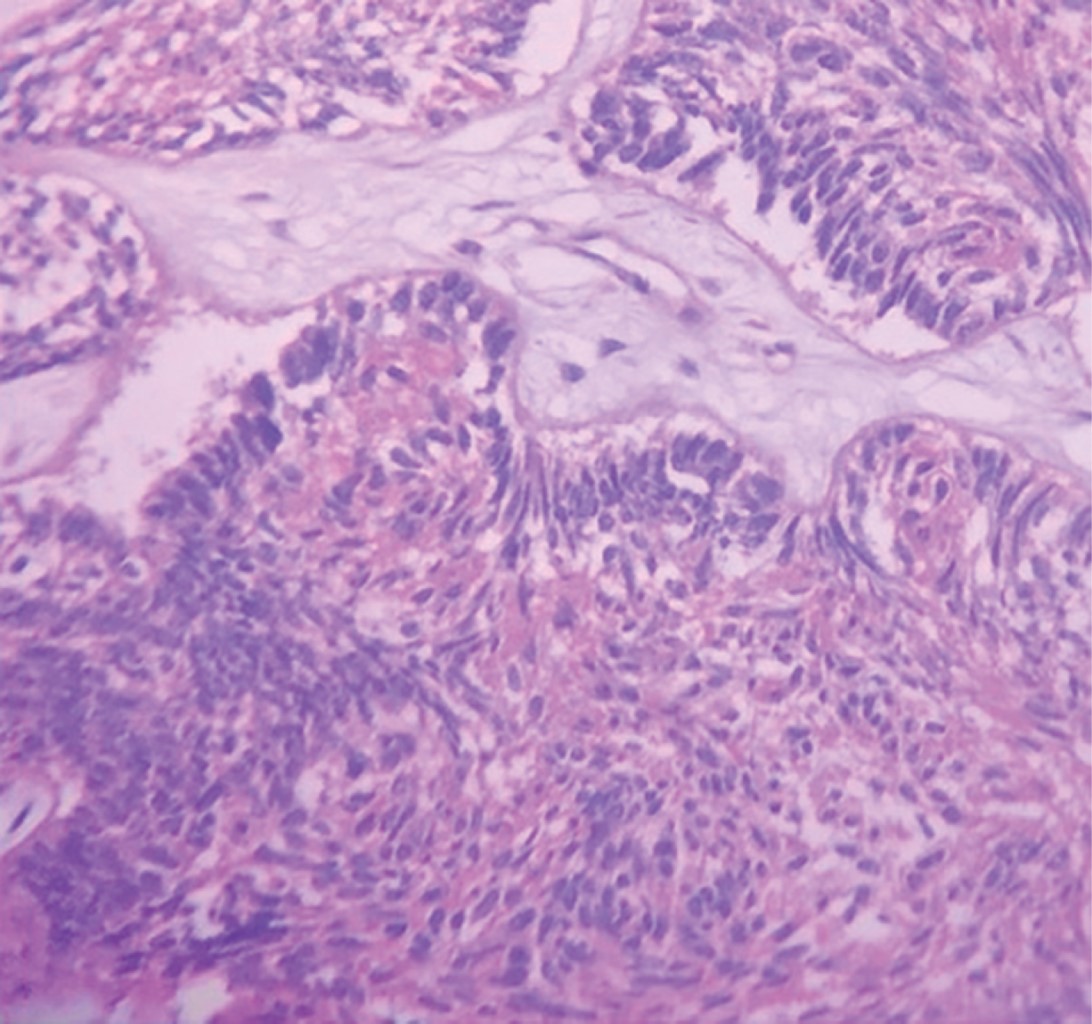

Inició padecimiento 19 meses previo a su primera valoración refiriendo chasquido súbito tras apertura máxima de la cavidad bucal, presentando dolor y aumento de volumen en la región posterior de la mandíbula derecha. En ortopantomografía se observa una zona radiolúcida, multilocular que abarca la rama ascendente derecha de la mandíbula y porción posterior del cuerpo mandibular con desplazamiento de tercer molar hacia borde cervical mandibular (Figura 1). En tomografía computarizada se observa lesión patológica multilocular que abarca la rama ascendente de la mandíbula, apófisis coronoides y hasta el cuello del cóndilo, la de mayor diámetro es de 35 × 32 mm con perforación de corticales casi en su totalidad y expansión de las corticales residuales (Figura 2). Se procede a realizar toma de biopsia incisional con un resultado de ameloblastoma folicular con datos de atipia celular (Figura 3), por lo que se decide solicitar gammagrama óseo que muestra una captación anormal en la rama mandibular derecha desde el cóndilo que correlacionan con la tumoración presente, así como un resultado negativo a la extensión metastásica ósea (Figura 4). Se decide realizar hemimandibulectomía y colocación de placa de reconstrucción con componente condilar. Se solicita estereolitografía para la preconformación de la placa de titanio y así disminuir el tiempo transoperatorio y márgenes de error en su colocación (Figura 5). Bajo anestesia general balanceada (AGB) se realizó fijación intermaxilar con ayuda de tornillos y cadena elástica. Se hizo incisión submandibular, se diseco el tejido por planos hasta llegar al hueso mandibular, se procedió a realizar hemimandibulectomía derecha, posteriormente se colocó placa de reconstrucción (Medartis MODUS®) con bloqueo y dispositivo condilar para reconstruir el cuerpo y rama mandibular (Figura 6), se verificó la oclusión, y el ajuste de la placa mediante toma de radiografía de control transoperatoria (Figura 7), se suturó por planos con sutura Vycril 3.0 y Polipropileno 5-0 para confrontar tejidos. El postoperatorio cursa sin complicaciones, por lo que se decide su egreso hospitalario para continuar su tratamiento por consulta externa en servicio de cirugía maxilofacial (Figura 8). El resultado histopatológico de la muestra completa reporta un espécimen formado por islas y cordones de epitelio ameloblástico de aspecto folicular y acantomatoso y displasia leve en un tejido conectivo fibroso denso bien vascularizado. Dos años después del procedimiento quirúrgico el paciente se encuentra asintomático y sin datos clínicos o radiográficos de recidiva.

Figura 3